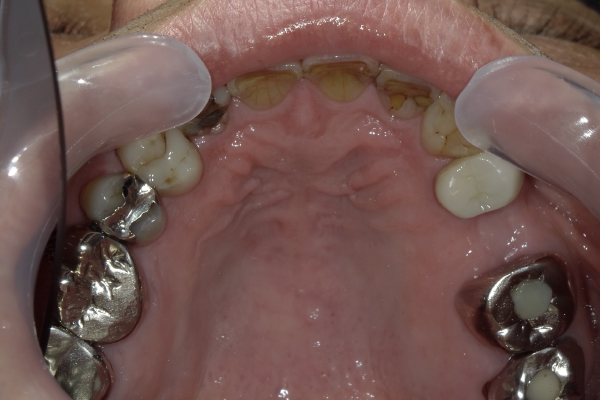

Case11

| 主訴 | 左上の歯が無い所にインプラントして欲しい |

|---|---|

| 治療期間 | 約3か月 |

| 治療費 | 950,000円 |

| 治療内容 | 左上に2本インプラント治療を行いました。骨の高さが不足していた為、ソケットリフトという、人工の骨を足して治療を行いました。 |

| 治療の リスク | インプラントも残っている歯と同様に歯周病になる可能性がある |